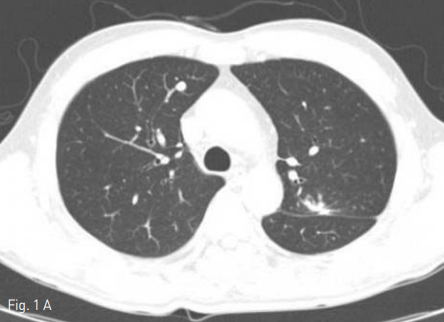

Supine position에서 시행한 cone beam CT(CBCT)상 right lung의 upper lobe에 위치하는 약 7mm 지름의 결절은 관찰가능하였다. 통증조절을 위해 Lidocaine국소 마취와 Midazolam 2mg i.v. 하였다. CBCT guide 하에 2개의 2.5cm Octopus electrode(STARmed, Kyeonggi-do, Korea)를 병변에 삽입하였으며, 이중 upper electrode가 병변을 관통한 상태였고, lower electrode는 제거하였다(Fig.2). 12분간 RF ablation을 시행하였으며, CBCT상 병변 주변으로 ground glass opacty(GGO)가 형성된 것을 확인하였다 (Fig. 3). 마지막 CBCT상 RF ablation 으로 인한 volume loss로 인하여 mediastinal pleura 가 병변쪽으로 deviation된 것이 관찰되었고, 출혈, 기흉 등의 합병증은 없었다. 시술 중 통증은 경미하였다.

Fig 3A

Axial & sagittal CBCT scan show post procedure ground glass opacity with sufficient safety margin. Mild retraction of right anterior mediastinum to the lesion may be shown. There was no evidence of pneumothorax or hemothorax.

Fig 3B